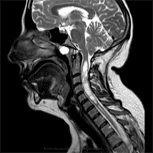

È allora facilmente comprensibile perché i nostri neurochirurghi raccomandano l’intervento alla maggior parte dei casi diagnosticati, e di sottoporvisi il prima possibile: il nostro metodo di trattamento elimina la causa della malattia, la quale agisce costantemente, ne arresta l’ulteriore sviluppo e permette che il sistema nervoso restauri le lesioni reversibili, senza che se ne producano altre o che arrivino a essere irreversibili, migliorando in tal modo la qualità di vita dei malati.

Dato che i benefici sono di gran lunga maggiori dei rischi, anche nel caso dei pazienti quasi asintomatici o senza limitazioni, si raccomanda di procedere subito alla sua applicazione, per evitare in tal modo un peggioramento del loro stato, che può avvenire per l’età, un trauma o una condizione scatenante, o semplicemente per lo stesso progresso naturale della patologia.